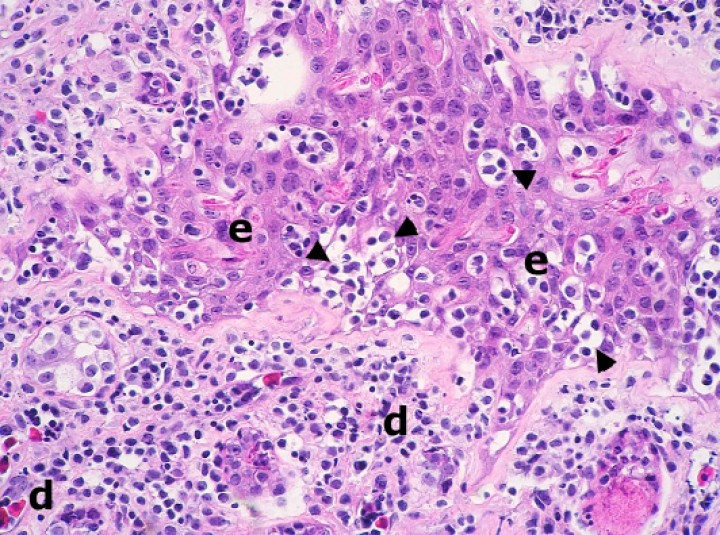

Se observaron 8 neoplasias, diagnosticadas en 6 de los 131 (4,6%) anfibios. Dos correspondían a adenocarcinomas sin evidencias de metástasis: uno intestinal en una rana dardo verdinegra (Dendrobates auratus) (Fig. 8), y otro en un tejido no identificable en un sapo buey (Rhinella schneideri); este último mostraba, además, hemangiomas en el pulmón (Fig. 9). El adenocarcinoma intestinal de la rana dardo verdinegra (Dendrobates auratus) consistía en una proliferación mal delimitada y no encapsulada de enterocitos que formaban criptas y glándulas variablemente dilatadas o, raramente, nidos diminutos compactos que invadían de forma amplia todas las capas del segmento intestinal afectado (Fig. 8) y mostraban anisocitosis, anisocariosis, pleomorfismo y anaplasia bajos a moderados, sin actividad mitótica aparente. Otros 3 anfibios padecieron neoplasias hematopoyéticas: un linfoma multicéntrico con componente epiteliotrópico en una rana tomate (Fig. 10) y dos neoplasias de células redondas no identificables de forma clara mediante la tinción rutinaria en un sapillo balear (Alytes muletensis) y un axolote (Ambystoma mexicanum). Otro sapillo balear (Alytes muletensis) mostraba una proliferación multicéntrica benigna de epitelio renal tubular (Fig. 11) organizado en estructuras tubulares, papilares y quísticas (Fig. 12), compatible con adenomatosis renal (adenomas múltiples); se observó atipia celular en escasas células neoplásicas y en células epiteliales de túbulos no neoplásicos. Adicionalmente, en este sapillo balear (Alytes muletensis) se apreció un foco hepático bien delimitado y no encapsulado de proliferación de hepatocitos compatible con hiperplasia nodular o un hepatoma; la ausencia de tríadas portales dentro de esta neoplasia es compatible con un hepatoma (Fig. 13).

<p>Piel; rana tomate (<em>Dyscophus guineti</em>). Con patrón difuso, la dermis (d) está densamente infiltrada por linfocitos pequeños neoplásicos acompañados por detritos nucleares; estos infiltrados forman además numerosos focos de epiteliotropismo caracterizados por la presencia de múltiples linfocitos dispuestos en pequeños nidos intraepidérmicos (cabezas de flecha). e: epidermis. Hematoxilina-eosina, x220.</p>

Figura 10

Piel; rana tomate (Dyscophus guineti). Con patrón difuso, la dermis (d) está densamente infiltrada por linfocitos pequeños neoplásicos acompañados por detritos nucleares; estos infiltrados forman además numerosos focos de epiteliotropismo caracterizados por la presencia de múltiples linfocitos dispuestos en pequeños nidos intraepidérmicos (cabezas de flecha). e: epidermis. Hematoxilina-eosina, x220.